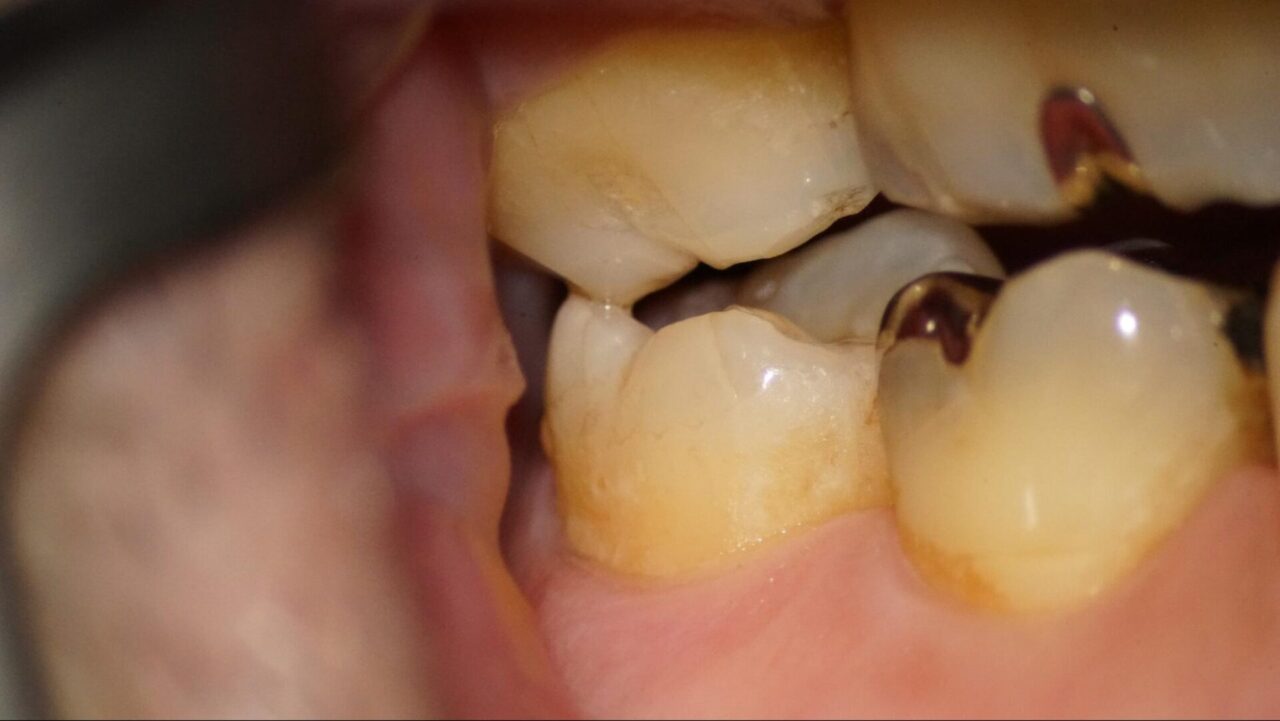

噛むとズキンとするという症状

噛むとズキンとするという症状があり、口腔内の写真を診ると左側上顎第2大臼歯部に歯牙破折を認める。また左側方運動時に下の歯との干渉があり、歯の咬合面や頬側面にクラックラインが確認する事ができる。